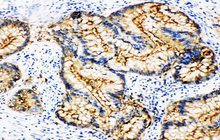

- General and specialized tissue and cell staining

- Immunohistochemistry (IHC) technique

Histological methods includes sample processing in the pathology laboratory, preparation of the slide and its examination under a microscope, sample fixation, molding, microtome cutting, staining and assembly of the slides.